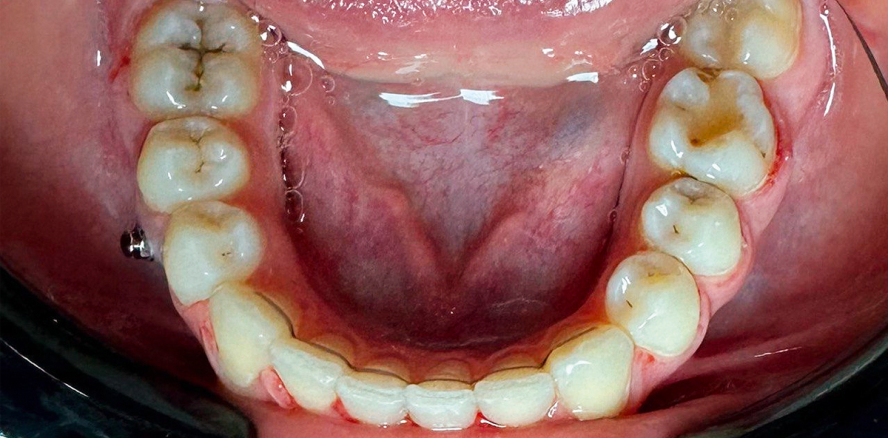

Abbildung 1 zeigt die Ausgangssituation: den Verlust des Zahns 46. Als Behandlungsansatz wurde entschieden, den benachbarten Zahn 47 durch gezielte kieferorthopädische Maßnahmen an die Stelle des fehlenden Zahns 46 zu verschieben. Zur Sicherstellung einer kontrollierten und stabilen Zahnbewegung kamen Miniimplantate (Abb. 2) sowie individuell angepasste kieferorthopädische Bögen zum Einsatz. Diese Maßnahmen ermöglichten eine präzise Steuerung der Bewegungsrichtung und eine effektive Verankerung während des gesamten Prozesses.

Die Behandlungsdauer betrug insgesamt 25 Monate. Während dieser Zeit konnte durch konsequente Anwendung der eingesetzten Hilfsmittel ein kontinuierlicher Fortschritt erzielt werden, wie in Abbildung 3 dokumentiert. Die Überwachung und Anpassung der eingesetzten Apparaturen erfolgten in regelmäßigen Abständen, um eine optimale Zahnachskontrolle und eine harmonische Eingliederung in den Zahnbogen sicherzustellen.

Das Endergebnis (Abb. 4) zeigt eine vollständige Wiederherstellung der Kauleistung, die ohne die Notwendigkeit einer Implantation erreicht wurde. Die erfolgreiche Verlagerung des Zahns 47 ermöglichte nicht nur die funktionelle Rehabilitation, sondern trug auch wesentlich zur Ästhetik und Stabilität des Zahnbogens bei.